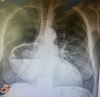

Mulher, 45 anos, dispneia e tosse seca há 5 dias. Passado de transplante pulmonar bilateral.

Bronquiolite obliterante (Bronquiectasias e espessamento das paredes brônquicas + Aprisionamento aéreo + Opacidades em vidro fosco -> Atenuação em mosaico)